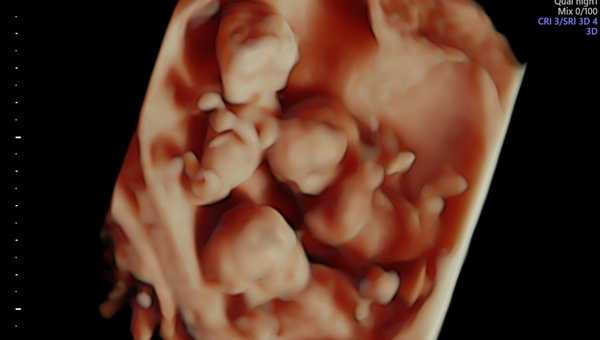

Скрининг показал, что врачи имеют дело с редчайшим случаем монохориальной триамниотической тройни. Это три плода, каждый из которых находится в своей амниотической полости, но в одной плаценте на троих. На практике это будет означать, что все дети будут на одно лицо.

Фото: Департамент здравоохранения Ханты-Мансийского городского округа — Югры